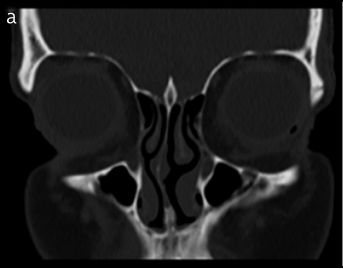

Results: The mean olfactory fossa depth was 5.63 mm. There was a statistically significant association (p<0.001) between olfactory fossa depth and the four indicators of excessive vertical facial growth combined. There was also an association between olfactory fossa depth and each indicator: facial index (p<0.001), saddle angle (p<0.001), SNA angle (p<0.001), and indicator line (p=0.001).

Conclusion: We found a statistically significant relationship between the four indicators of excessive vertical facial growth and the depth of the olfactory fossa. These results support our hypothesis, which states that the middle face drops in vertical facial growth, creating a gap in the olfactory fossa. Our results compel otolaryngologists to thoroughly check the depth of the olfactory fossa when treating patients with excess vertical facial growth scheduled for endoscopic sinus surgery.